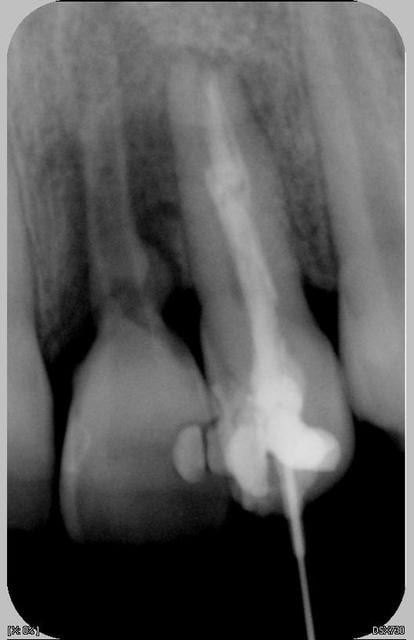

Patiente de 11 ans ayant la 21 expulsée début avril 2006. La dent a été repositionnée en centre de soins. Dans un premier temps, pas de perte de sensibilité. Puis dans un deuxième temps, comme un goût de ça tourne mal avec certainement rhyzalyse interne de la 22 (traitement thermafil pas d'école).

la on est dans un tres beau cas de resorption inflammatoire des 21 et 22

la 22 :evident,reprise du traitement endo

La 22 n'était pas cariée, simplement en rotation (elle l'est encore)avec une anatomie atypique (angle mésio-occlusal très fin).

Le milieu est extémement infecté et la résorbtion de la 21 n'est pas aseptique : donc je ne peux pas attendre.

Mon collègue en mon absence a essayé de traiter la 22 et mis un composite pour éviter l'expulsion de la 21. Souvent on fait comme on peut et je sens que la critique va fuser tel la pierre qui ricoche. que celui qui n'a fait que des traitements de rêve la lance.